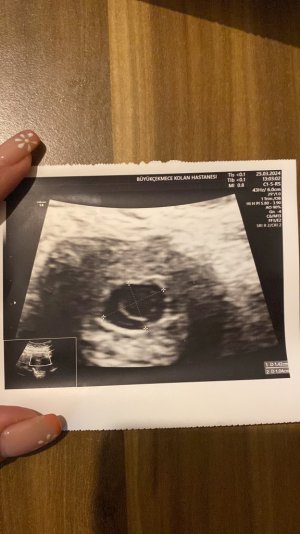

19 Mart’ta gebelik kesem 1.38 cm idi pazartesi gel ve kalp atışına bakalım dedi doktorum ve bugün gittik keseye baktı ve kalp atışı henüz oluşmamış dedi. Kese ölçüm 1.42 cm bugün.

Daha sonra önceki ölçü ile kıyaslayınca “öncekine göre kese etrafı kalınlaşıp şekillenmiş ancak kese olması gerektiği kadar büyümemiş 5 günde 1 günlük ilerlemiş” dedi ve sonrasında kaybediyor olabiliriz dedi kan testi ver beklemene gerek yok 2 gün sonra tekrar ver ikisini kıyaslayacağız dedi. En son 8 martta beta baktırdığımda 1794 idi. Bugünkü beta testi sonucum 3350. Beta değerim de az gibi geldi ama bilmiyorum. Bu arada bugüne kadar her kontrolde olması gerekenden ileride olduğumuzu söylüyordu 19 martta tam günümüze denk geliyorduk ama şuan hiç bir gelişme yok bu durum beni korkutuyor. Sancı ya da kanama yaşamıyorum. Aynı ya da benzer durumu yaşayanlar var mı?

19 Mart’ta gebelik kesem 1.38 cm idi pazartesi gel ve kalp atışına bakalım dedi doktorum ve bugün gittik keseye baktı ve kalp atışı henüz oluşmamış dedi. Kese ölçüm 1.42 cm bugün.

Daha sonra önceki ölçü ile kıyaslayınca “öncekine göre kese etrafı kalınlaşıp şekillenmiş ancak kese olması gerektiği kadar büyümemiş 5 günde 1 günlük ilerlemiş” dedi ve sonrasında kaybediyor olabiliriz dedi kan testi ver beklemene gerek yok 2 gün sonra tekrar ver ikisini kıyaslayacağız dedi. En son 8 martta beta baktırdığımda 1794 idi. Bugünkü beta testi sonucum 3350. Beta değerim de az gibi geldi ama bilmiyorum. Bu arada bugüne kadar her kontrolde olması gerekenden ileride olduğumuzu söylüyordu 19 martta tam günümüze denk geliyorduk ama şuan hiç bir gelişme yok bu durum beni korkutuyor. Sancı ya da kanama yaşamıyorum. Aynı ya da benzer durumu yaşayanlar var mı?